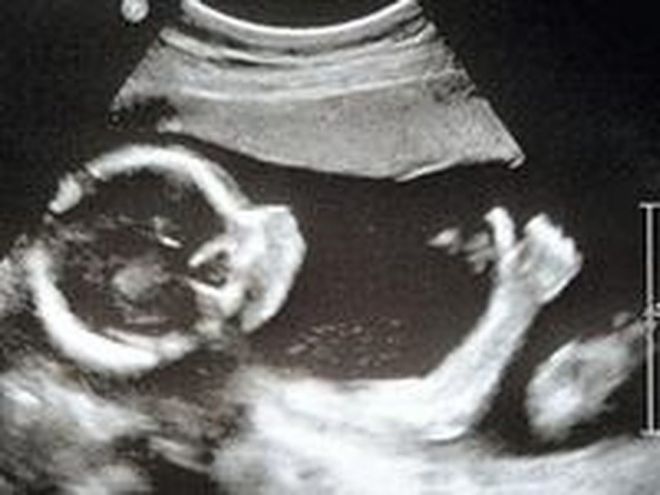

Բնավորությունը առաջ է գալիս մանկուց։